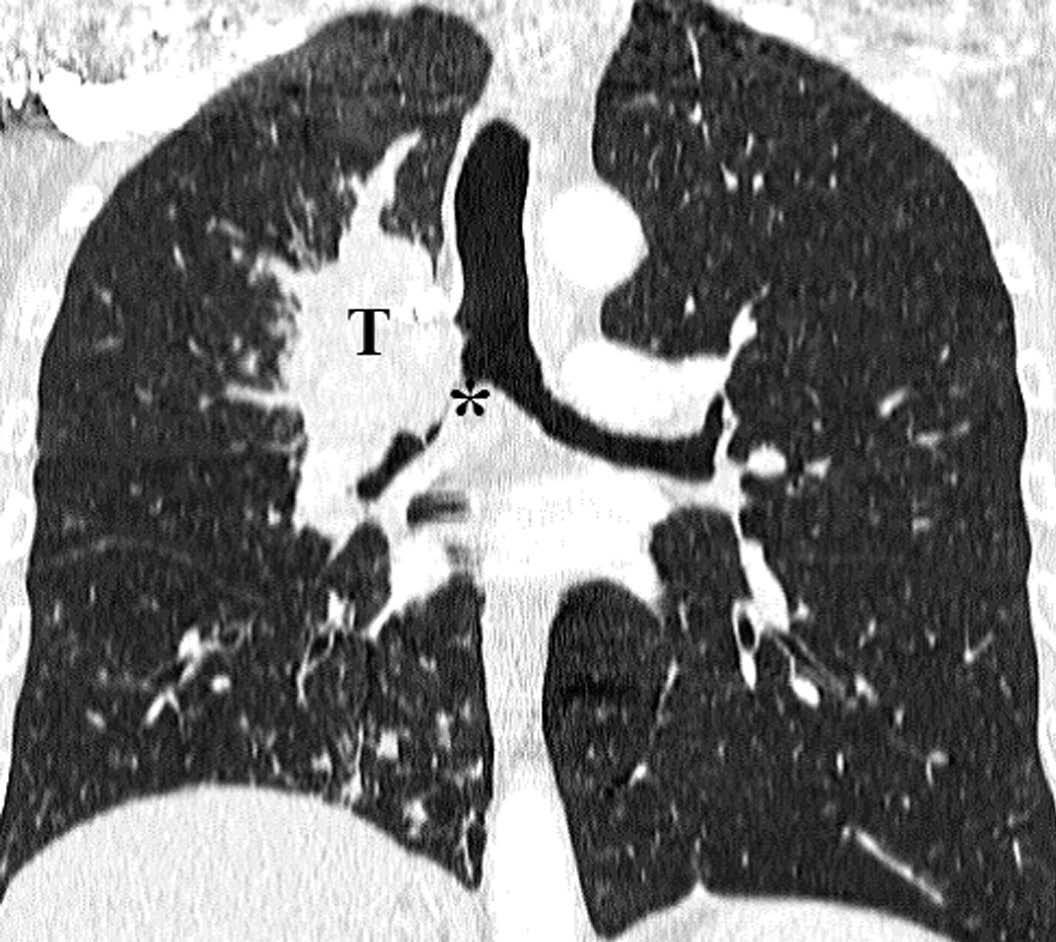

Pese a las conocidas limitaciones de la TC, ésta continúa siendo la técnica de elección en la estadificación del tumor en los pacientes con CPNM; su sensibilidad y especificidad en la determinación de la infiltración de pared oscilan entre el 38 y el 87% y del 40 al 90%, respectivamente, según las series. El desarrollo de nuevos equipos de TC helicoidal y principalmente las TC multidetectoras (TCMD) proporcionan unas imágenes 2D de mayor resolución con la posibilidad de hacer reconstrucciones multiplanares (MPR) en distintos planos del espacio e incluso 3D con la consiguiente mejora de la valoración del tumor, su extensión e infiltración de estructuras vecinas5 (fig. 4). Así, con la TCMD se puede poner de manifiesto con mayor fiabilidad la invasión de la cisura, la pared torácica o el mediastino, y además es capaz de determinar, gracias a las reconstrucciones de volumen, la relación exacta del tumor con la vía aérea (fig. 5). El progreso en la capacidad diagnóstica deriva del incremento en la resolución de las imágenes obtenidas y de la posibilidad de emplear nuevas aplicaciones como la broncoscopia virtual y la visualización en tiempo real. La broncoscopia virtual es útil para valorar la invasión del árbol traqueobronquial con la finalidad de planificar la cirugía, también como guía para el fibrobroncoscopista y, por último, porque permite ver el árbol bronquial distal a la estenosis (fig. 6)6. La capacidad de ver la imagen en tiempo real es especialmente útil cuando se emplea como guía en maniobras intervencionistas como biopsias percutáneas, ya sea con finalidad diagnóstica o como parte de la estadificación (fig. 7). Esta técnica de guía de biopsia denominada TC fluoroscopia reduce el número de pases y el tiempo global de la exploración, implica un menor riesgo de lesión de estructuras y permite la visualización inmediata de las posibles complicaciones7.

Fig. 6.--Broncoscopia virtual. (A) Reconstrucción coronal que muestra una masa hiliar derecha (T) con infiltración del ángulo traqueobronquial. (B) Visión endoscópica del tumor en la que se observa la infiltración de la tráquea y la relación con la carina (asterisco).